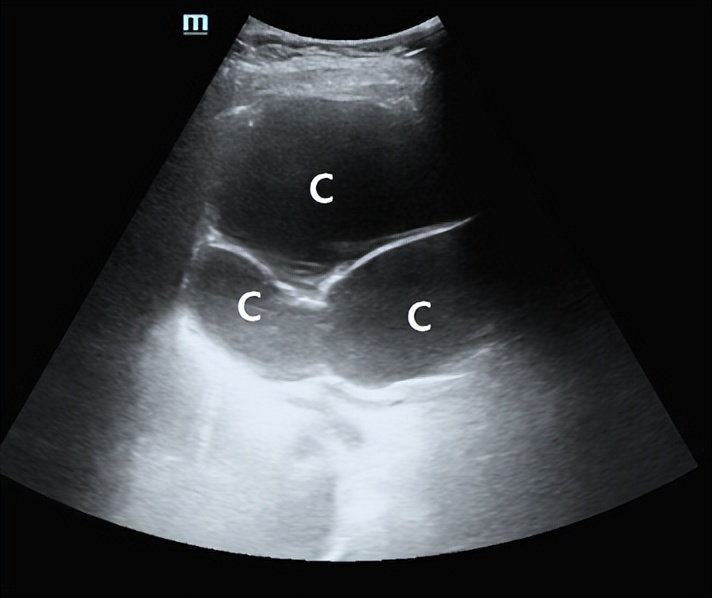

超声:肝内多发囊肿

介入超声治疗方案:对最大的囊肿进行超声引导下经皮穿刺置管引流,对其他直径<8cm的囊肿分别进行穿刺抽液、硬化治疗。

首先对最大的囊肿进行置管引流。超声确定最佳穿刺路径,消毒铺巾,上穿刺架,调整引导线,18G PTC针进入囊肿中心,置入导丝,扩皮,置入猪尾管持续引流,返回病房。